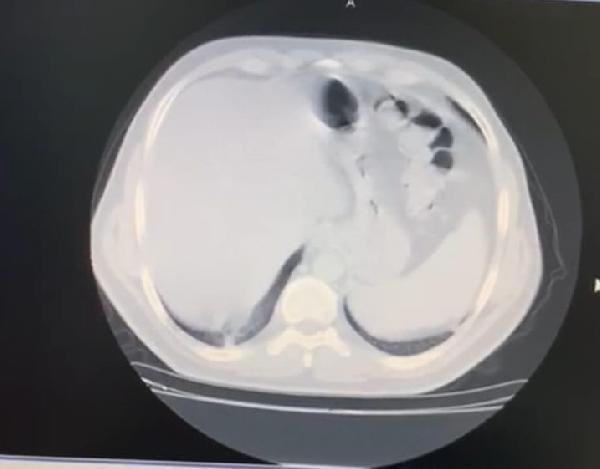

Yoğun kas ağrısı şikayeti olan İç Hastalıkları Uzmanı Celal Civil, akciğer tomografisinin ardından koronavirüse yakalandığını fark etti. 8 gün evde tedavi gören Civil’in durumu kötüye gitmeye başladı. İkinci tomografisinde koronavirüsün akciğerinin yüzde 70’ini kapladığı görülen genç doktor, yaklaşık 1 aylık tedavisinin ardından sağlığına kavuşarak görevine döndü.

AKCİĞERİN YÜZDE 70’İNDE TUTULMA GÖRÜLDÜ

Evdeki 8 günlük sürecin ardından durumu ağırlaşan Civil, ikinci kez çekilen tomografide akciğerinde yaygın bir koronavirüs zatürre tutulumu görüldüğüne dikkat çekerek şunları söyledi; “Çok korkunç bir görüntü vardı. O görüntüyü görünce psikolojik olarak da çok etkilendim. Daha sonra hastaneye yatırıldım ve ateşim 41 derece civarındaydı. Oksijen satürasyonum da 70’lere kadar düştü. Yoğun bakım hastalarında kullanılan bir ilaca başlandı. Hastaneye yattığımın ilk 3 günü çok kritikti. Genel durumum bu 3 gün içerisinde yavaş yavaş bozulmaya başlamıştı. Nefes alamıyordum ve boğuluyordum. Sıkıntılı ve sancılı bir süreçti"

Tomografisinde görülen bulguların ne anlama geldiğini bildiği için ümitsizliğe kapıldığını ifade eden İstanbul Gelişim Üniversitesi Sağlık Bilimleri Yüksekokulu’ndan Dr. Öğretim Üyesi Celal Civil, “Vital bulgularım çok kötüydü. Acaba bu virüsü atlatamayacak mıyım? Yolun sonuna mı geldik? Buraya kadar mı? diye çok düşündüm. Klinik olarak kötü durumdaydım, radyolojik ve laboratuvar sonuçlarım da çok kötüydü. Nefes darlığı çok kötü bir duygu. Boğulma hissi yaşıyorsunuz. Boşuna nefes alıyormuş gibi hissediyorsunuz çünkü ciğerler koronavirüs tarafından tutulmuş durumda. Kafanızı suya sokup nefes almaya çalışmaya benziyor. Dakikada 8 litre oksijenle hayata tutunmaya çalışıyordum. 1 hafta boyunca oksijene bağımlı bir şekilde hastanede yattım. İlk günler dip yaşadım, hatta 2 kez yoğun bakım ekibi benim için geldi, entübasyon dahi düşünüldü” dedi.